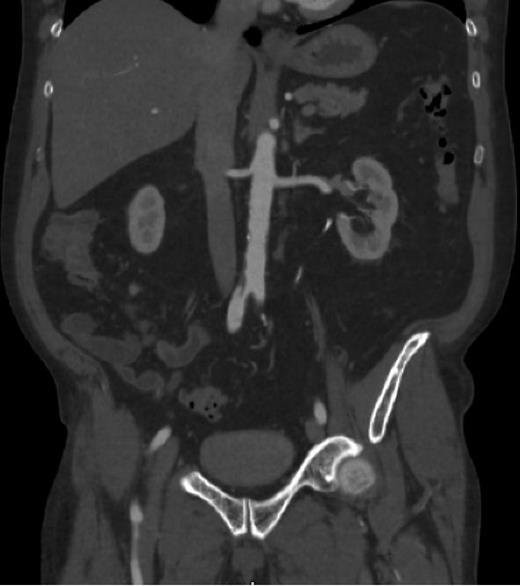

Spontaneous iliac artery dissection (IAD) is a rare medical condition with only a few cases being reported in the medical literature. Dissections typically involve the aorta and are not localized to the iliac arteries. Patients with spontaneous IAD typically present with symptoms that resemble peripheral artery disease, and cases are typically associated with connective tissue diseases such as Marfan syndrome and Ehlers-Danlos syndrome or high-risk states such as pregnancy and extreme athletics. There are some case reports that showed an association with hyperlipidemia, hypertension, and tobacco use. The most frequent complication of spontaneous IAD is rupture, and cases are typically treated endovascularly but may be treated with classical surgery such as in the case of rupture. Some cases have reportedly been treated with conservative management alone. In this case, we discuss a 66-year-old male with a past medical history of hyperlipidemia, hypertension, and tobacco use with no known diagnosis of connective tissue disease, and not in a high-risk state, who was found to have a spontaneous iliac artery dissection. He initially presented with sudden onset back pain that he described as a shooting pain that radiated into his head. He was also having right lower extremity discomfort. Initial vital signs were significant for tachycardia and hypertension, and physical exam was significant for tachycardia and diminished right posterior tibial and dorsalis pedis pulses. Laboratory workup was significant for a leukocytosis of 10.06 and creatinine of 1.52, consistent with acute kidney injury. Labs were otherwise unremarkable. Computed tomography angiogram (CTA) of the head and neck was negative for acute pathology, but CTA chest/abdomen/pelvis demonstrated arterial dissection that began at the origin of the right common iliac artery extending down to the right common femoral artery and also demonstrated a left renal infarct. A bare metal stent was placed by Interventional Radiology and the patient was started on dual antiplatelet therapy (DAPT) with a heparin drip and clopidogrel. Connective tissue disease workup was later performed including antinuclear antibody, rheumatoid factor, cyclic citrullinated peptide, and extractable nuclear antigen antibodies panel, which were all negative. Hospital stay was complicated by development of subarachnoid hemorrhage, intraventricular hemorrhage, subdural hematoma, and intradural hematoma that required laminoplasty and evacuation by Neurosurgery. DAPT was discontinued and the patient was later restarted on aspirin only. The patient then developed a cecal bleed that required clipping by Gastroenterology. Aspirin was discontinued and he then developed bilateral lower extremity deep venous thromboses and pulmonary emboli. He was started on enoxaparin with the assistance of Hematology and was later transitioned to apixaban with no complications. This case supports comorbidities as risk factors for spontaneous IAD and raises the need for formal screening and surveillance guidelines for these patients, as there are currently no guidelines in place. This case also demonstrates the complications that can occur with DAPT and anticoagulants and provides a manner in which to cautiously initiate anticoagulation in patients with high risk of bleeding while also preventing the development of further thrombi.